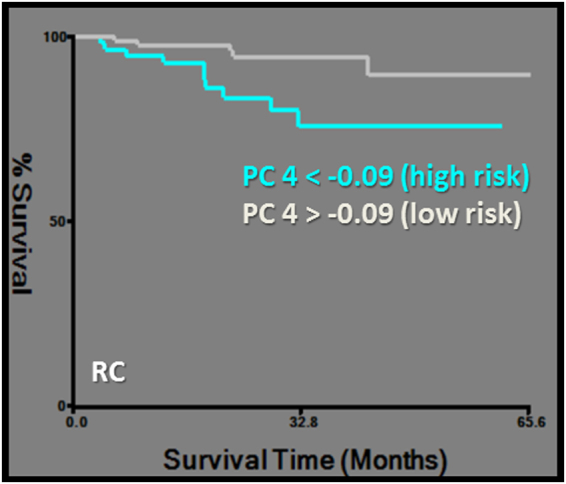

DSS was predicted by PC2, which was exclusively based on CT-derived first order and morphological features, namely the asymmetry group. The same first order features were also clustered in PC1 and PC2 (Tables 2, 3, 4, Fig. 4). RC was predicted by PC4, which is described above (Tables 2, 3, 4, Fig. 5).

Figure 5.

Kaplan-Meier survival curve for regional control (RC). Subgroups of low and high risk were determined by a cut-off value of −0.09 for PC4 (logrank chi-square: 6.19, p = 0.01).